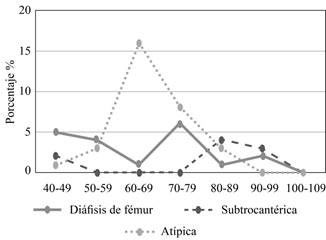

La distribución de la ubicación de las fracturas varía de acuerdo con los grupos de edad. Las FS presenta una distribución dual, siendo mayor a los 40-49 años y, posteriormente, a los 80-99 años; las FD tienen una presentación máxima a los 70-79 años seguido de personas comprendidos entre los 40-49 años; y las FAF se presentan principalmente a la edad de 60-69 años y 70-79 años (Figura 4).